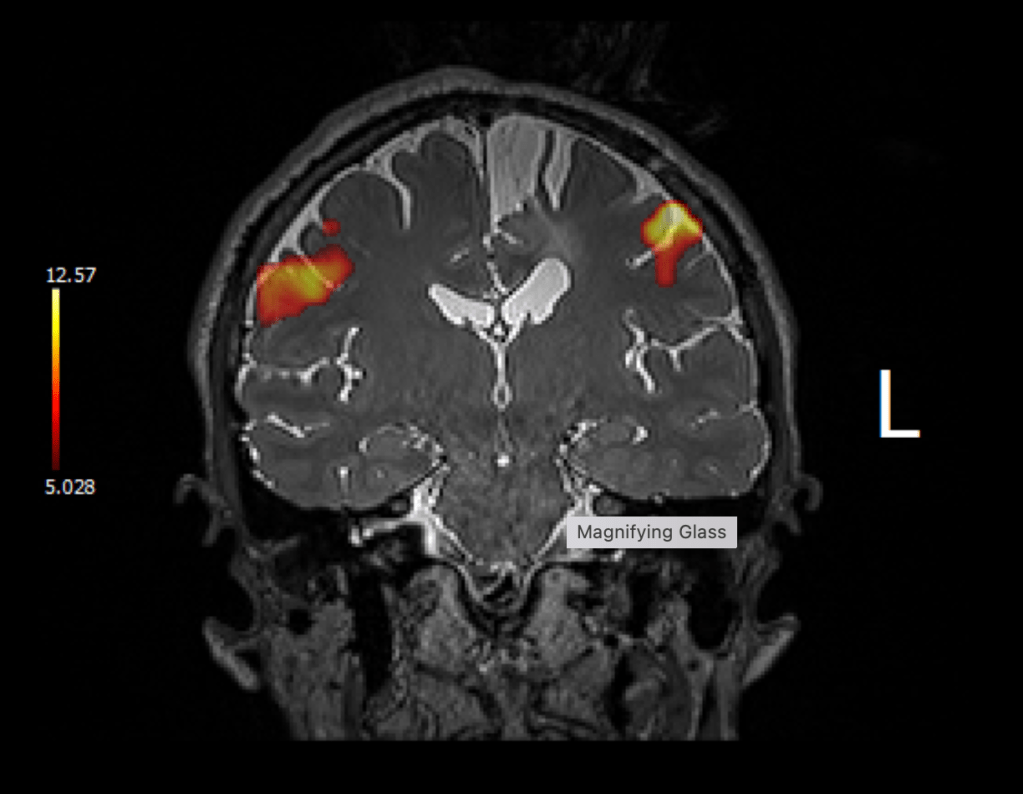

Well, I may have jumped the gun. Last Tuesday I had a functional MRI, which looks at which parts of the brain correlate to different actions. We did the following tests:

The most important result was the following:

The above image shows that my hand motor function is just next to the tumor.

When my Mom and I discussed these results via Zoom with Dr Bi on Thursday, she said, she thinks she can get the tumor out without any permanent functional loss or weakness. My Mom and I looked at each other slightly stunned, not knowing what to say. I had an entire list of questions regarding permanent disability, and they all became (cross our fingers), irrelevant.

A few important things to mention, however, to keep us grounded. One, fMRIs are rough indicators, so she will not truly know what is going on until she is mapping my brain with the electrodes I explained in my last post. And two, she expects I will wake up with weakness and need to do rehab to get back to where I am now (potentially more so than my 2018 surgery).